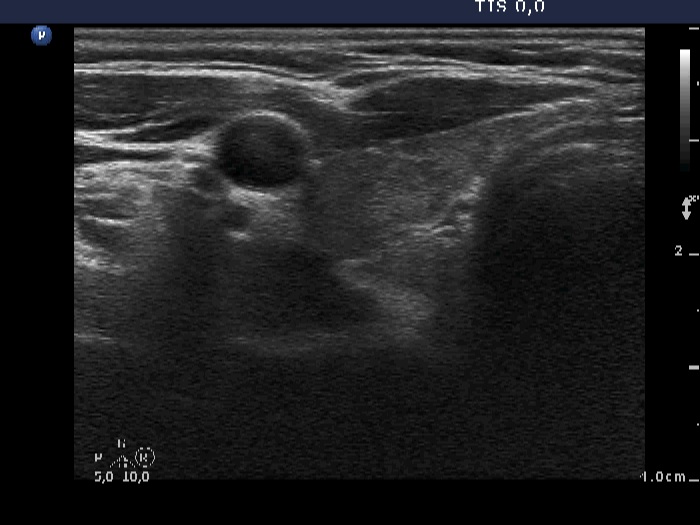

Ultrasonography: The thyroid was minimally-moderately hypoechogenic and presented fibrosis. There was a cystic lesion in the lower dorsal part of the right thyroid bed.

Twelve mL cystic fluid was aspirated. There were no cells on the smear.